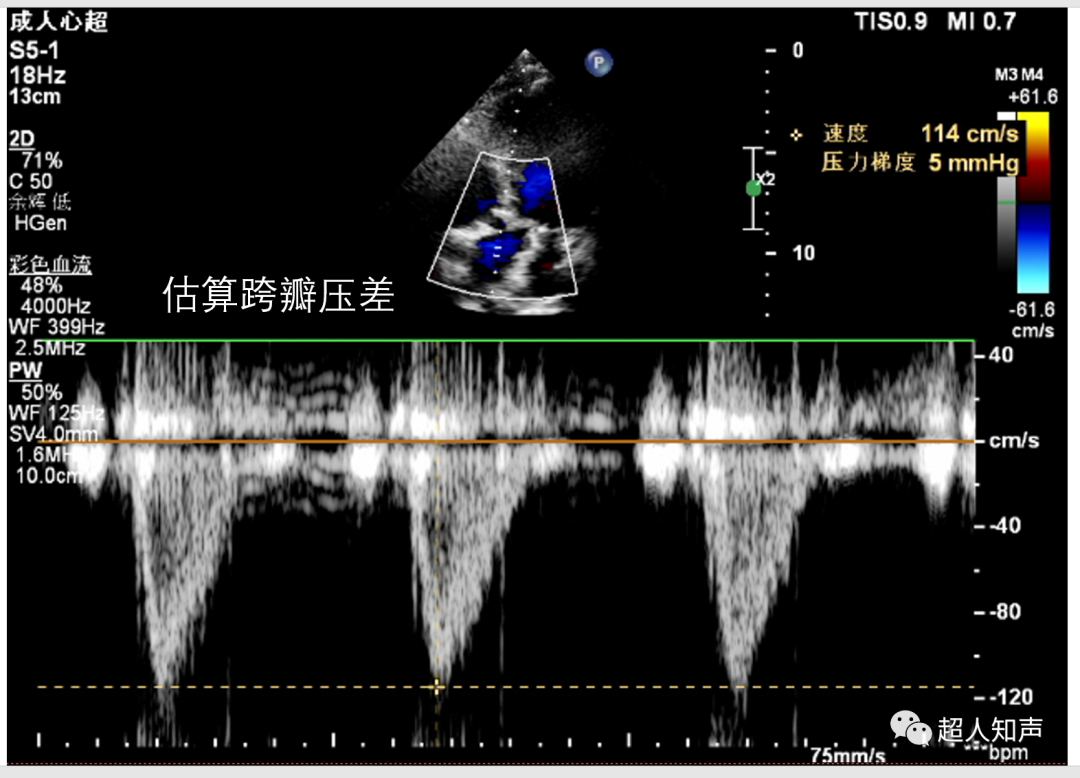

9.测量跨瓣压差。可利用简化伯努利方程△P=4Vmax2计算,△P即压差(PG),Vmax为Vp,单位是m/s。(如下图:PG=4×1.142≈5mmHg)